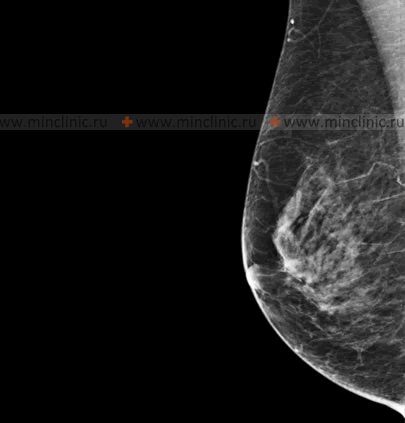

Fibroadenoma of the Breast

Nature and Clinical Features

A fibroadenoma of the breast is the most common type of benign breast tumor, composed of both fibrous (stromal) and glandular (epithelial) tissue. Fibroadenomas are considered a form of nodular mastopathy in women. Their development is often influenced by hormonal factors, particularly estrogen. Hormonal imbalances, such as those that may be present in some patients with menstrual irregularities (dysmenorrhea), can create a favorable background for the occurrence or growth of breast fibroadenomas.

Clinically, a fibroadenoma of the breast typically presents as a firm, well-defined, rounded or oval-shaped lump (knot) that is dense on palpation. When examined by a mammologist or physician, a fibroadenoma usually feels like a painless (though sometimes slightly tender), elastic or rubbery, smooth-surfaced formation. A key characteristic is its high mobility within the breast tissue; it is often described as being "slippery" or "mouse-like" as it can be easily moved around and is not attached to the overlying skin or underlying chest wall. The size of a fibroadenoma can range from very small (e.g., 0.5 cm) up to 5-7 cm in diameter, or occasionally larger (giant fibroadenoma). It is fibroadenomas that are most often self-detected as a palpable lump by young women, often those also experiencing menstrual irregularities.

While fibroadenomas are benign and do not typically increase the risk of breast cancer, any new breast lump should be evaluated by a healthcare professional to confirm the diagnosis and rule out malignancy.